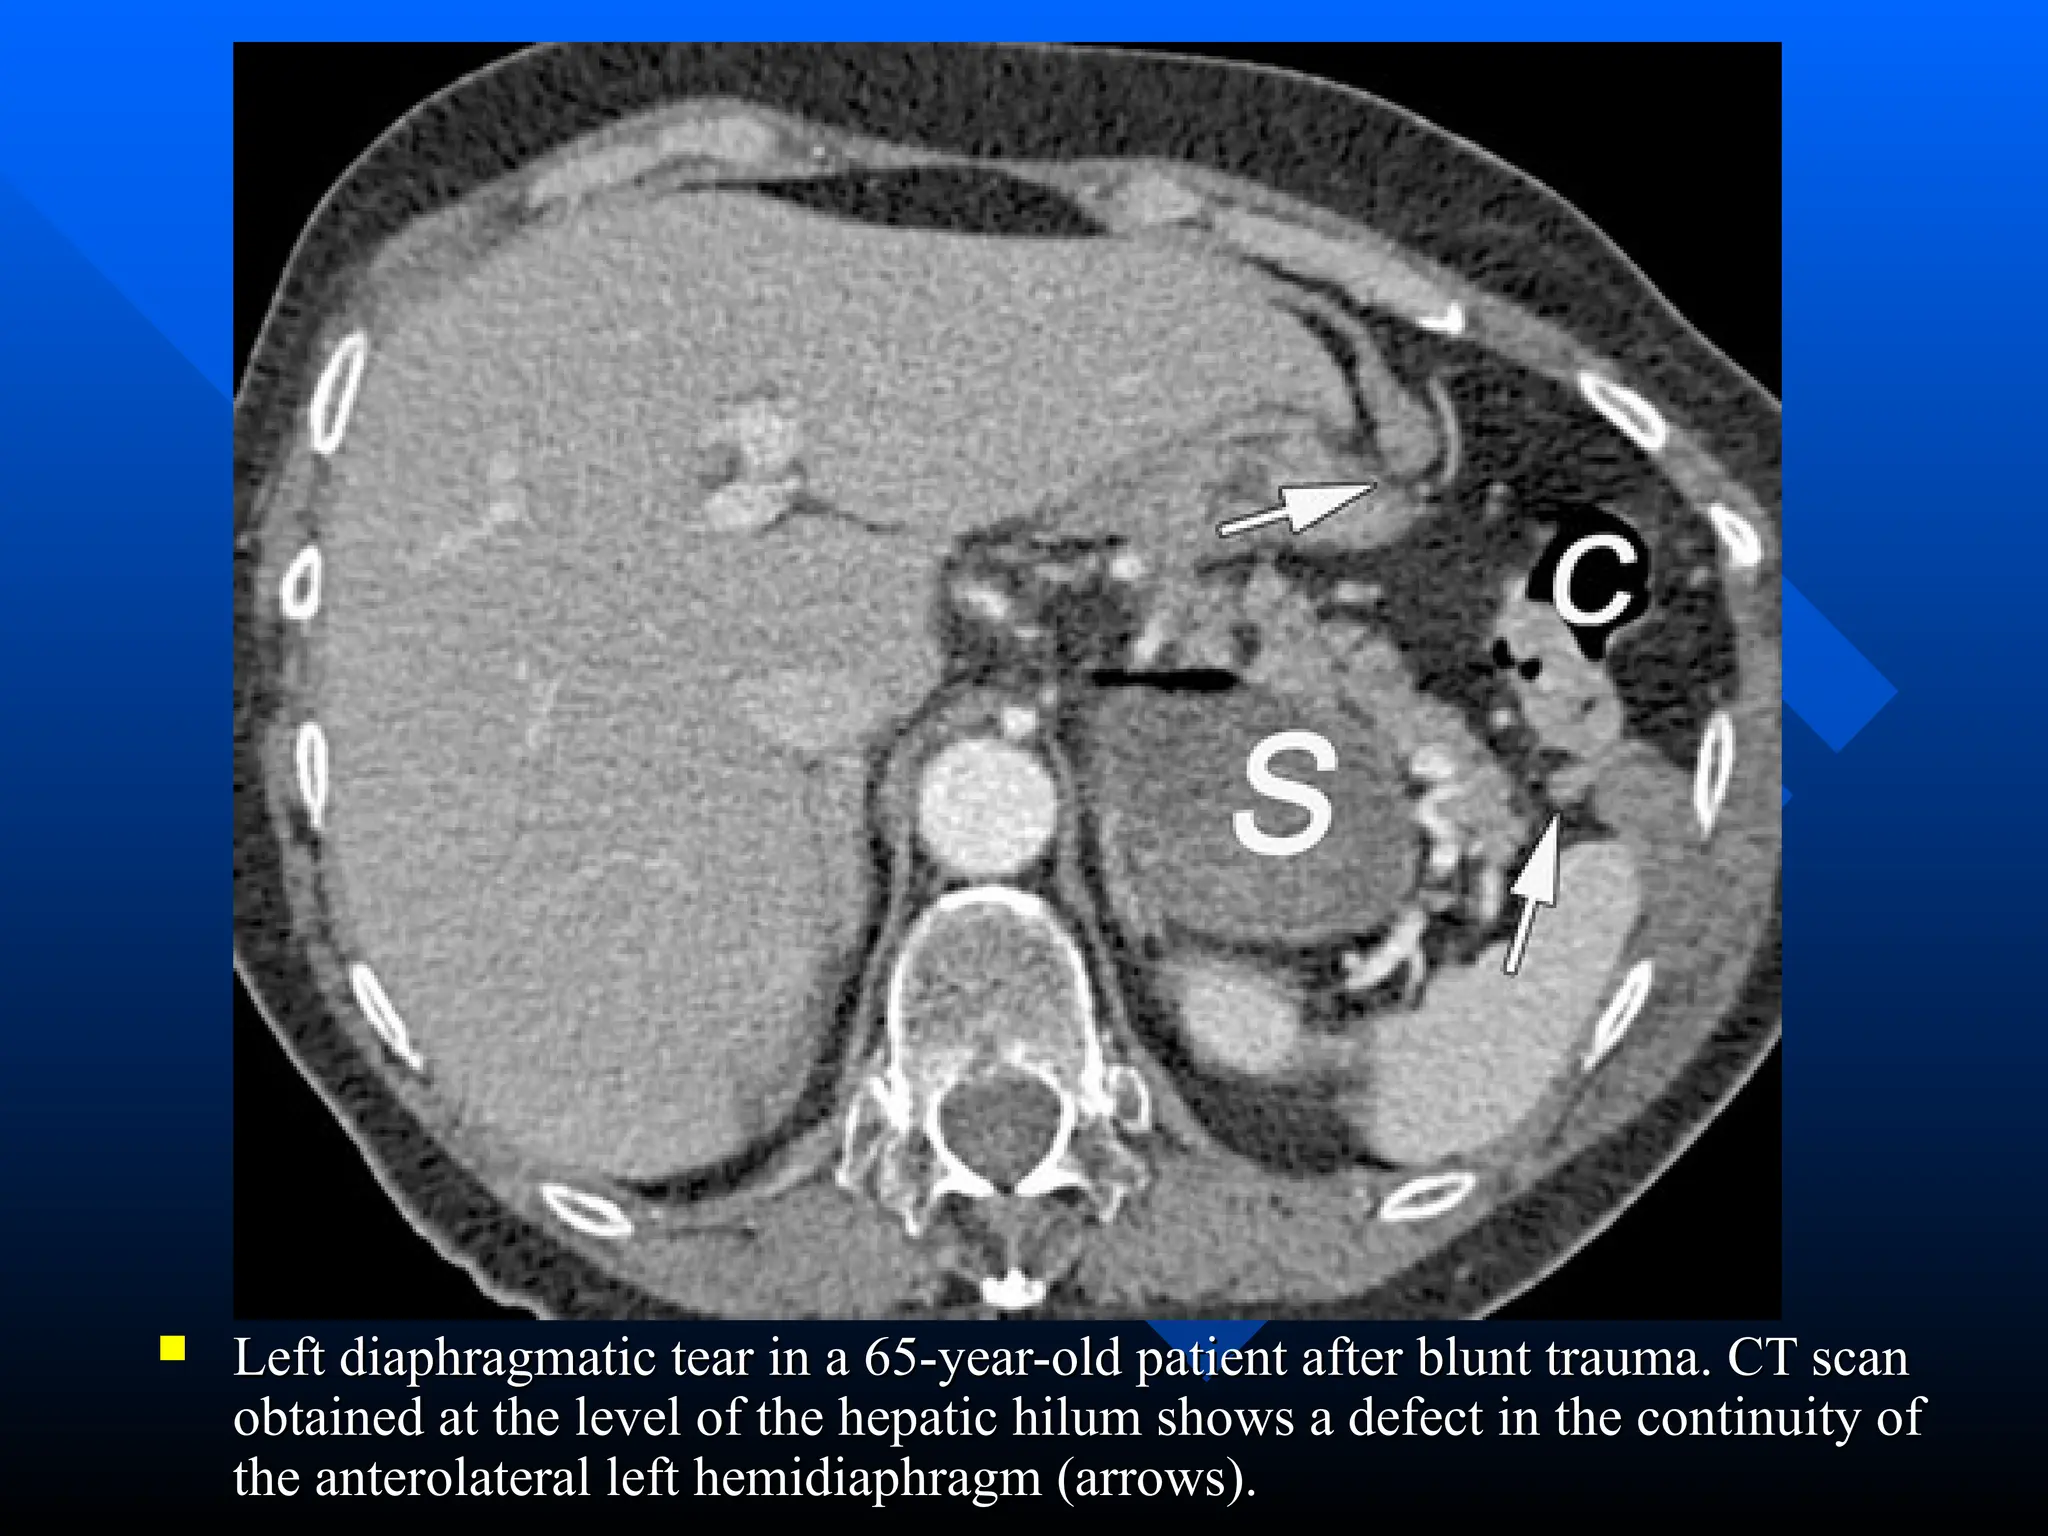

 Left diaphragmatic tear in a 65-year-old patient after blunt trauma. CT scan

Left diaphragmatic tear in a 65-year-old patient after blunt trauma. CT scan

obtained at the level of the hepatic hilum shows a defect in the continuity of

the anterolateral left hemidiaphragm (arrows).